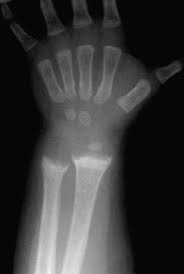

Krivica alebo rachitída (rachitis) je ochorenie, ktoré sa prejavuje u detí. Je vyvolané nedostatkom vitamínu D, ale často býva spôsobená aj nedostatočnou výživou, najmä "chudobnou" na tento vitamín, ale aj nedostatkom slnečného žiarenia, pomocou ktorého dokáže telo vytvárať samé vitamín D.